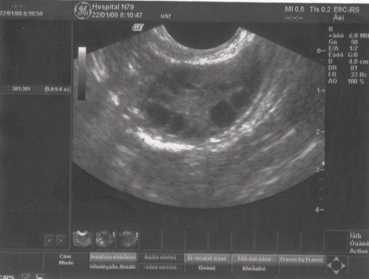

Маточная беременность малого срока

Рис. 3. Маточная беременность 7-8 недель.

Размеры плодного яйца и эмбриона соответствуют сроку задержки менструации.

При беременности в полости матки визуализируется на ранних сроках только плодное яйцо, в дальнейшем, появляется эмбрион. Размеры плодного яйца и эмбриона должны соответствовать сроку беременности по менструации.

Обязательной является также и оценка сердцебиения у плода, которое, как правило, появляется уже после 10-14 дней задержки менструации.

При беременности в одном из яичников должно визуализироваться желтое тело беременности, которое контролирует развитие данной беременности и обеспечивает на ранних сроках (до формирования плаценты) жизнедеятельность плода.